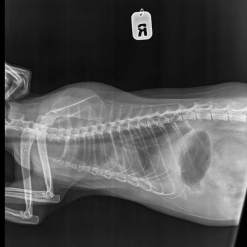

Срочный сбор на рентген 2 проекции 1400 руб. для Шурочки. ( завтра ).

Она сидит сгорбив спину ( больно), думали почки или печень.

А сегодня в клинике ее положили на спину и у нее начался жуткий кашель,

пришлось ставить укол от кашля. Похоже в нее стреляли ( как пулька на ребре прощупывается)

По рентгену пуль нет, а есть старый перелом грудины, небольшое количество жидкости в грудной области, очаговый ателектаз правого легкого, хр. бронхит, увеличена печень. В понедельник записались на УЗИ ( 600 руб.)